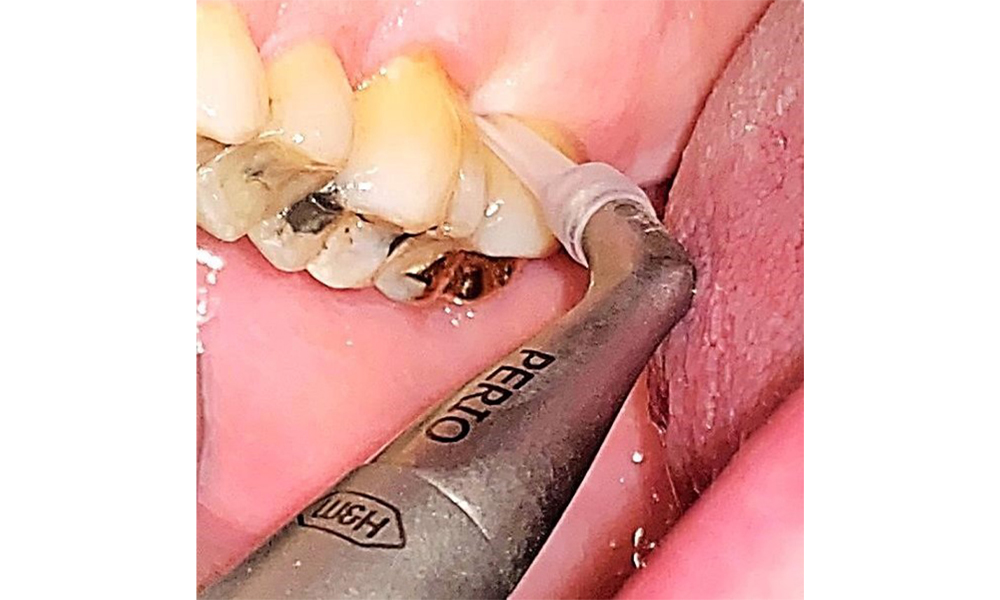

Nu există limitări în ceea ce privește alegerea metodelor de instrumentare. Sunt esențiale intervențiile subgingivale și supragingivale regulate, pentru prevenirea progresiei bolii - datorită parodontozei preexistente și a riscului ridicat de recidivă. Nu există limitări privind alegerea instrumentelor pentru îndepărtarea mecanică a biofilmului dintr-o perspectivă medicală generală, iar îndepărtarea trebuie efectuată în funcție de necesități. Placa dură și mineralizată, cum ar fi tartrul și concrețiunile, trebuie îndepărtate cu ajutorul pieselor de detartraj manuale sau al scalerului sonic/ultrasonic (Fig. 9) (8, 9).